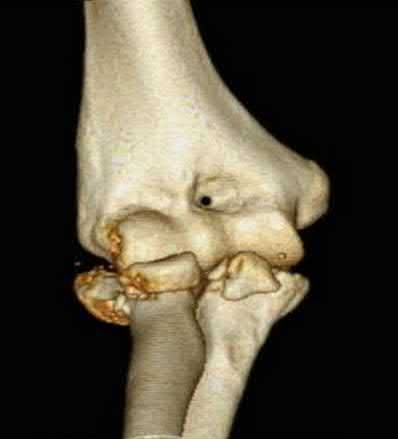

Question 11:

Correct Answer: Greater trochanters

Explanation:

For optimal mechanical advantage and effective reduction of an 'open book' pelvic fracture (APC type), a pelvic binder must be applied directly over the greater trochanters of the femurs. Applying it higher, such as over the iliac crests, is a common error that fails to adequately close the pelvic ring and can paradoxically open the true pelvis.